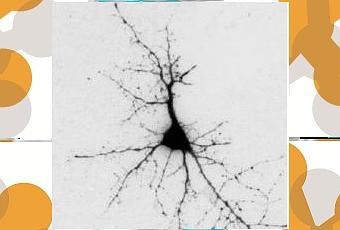

C’est en examinant les neurones cholinergiques pour essayer de comprendre pourquoi ils étaient endommagés si tôt et étaient parmi les premiers à mourir au cours du vieillissement normal mais aussi en cas de maladie d’Alzheimer, que les chercheurs ont identifié l’amyloïde chez de jeunes participants. Leur étude portait sur 3 groupes de personnes décédées: 13 jeunes sujets en bonne santé cognitive âgés de 20 à 66 ans, 16 sujets plus âgés (de 70 à 99 ans) exempts de démence et 21 sujets âgés de 60 à 95 ans, atteints de la maladie d’Alzheimer. C’est alors que les scientifiques ont découvert des molécules amyloïdes commençant à s’accumuler dans le cerveau des plus jeunes participants, dès l’âge de 20 ans. Précisément, ils identifient de petits amas toxiques, sous forme d’oligomères amyloïdes. La taille de ces amas s’accroît chez les personnes âgées et les personnes atteintes d’Alzheimer.

Ces résultats expliquent pourquoi les neurones cholinergiques touchés par ces amas meurent en premier mais suggère aussi que la pathogenèse de l’Alzheimer débute très tôt dans la vie. Ces touffes d’amyloïde vont sécréter de l’amyloïde extérieur de la cellule, ce qui contribue à la formation des grandes plaques amyloïdes typiques de la maladie d’Alzheimer.